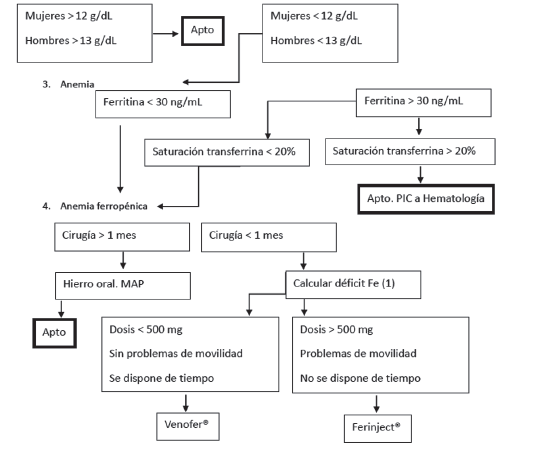

Guillermo Andres Martinez Salinas, Julio Yarmuch Gutierrez, Carlos Romero Patiño, Barbara Carreño Manriquez

|

|